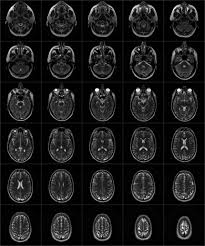

L'irm (imagerie par résonance magnétiques) est un examen qui permet d'étudier avec une grande précision de nombreux organes tels que le cerveau, la colonne vertébrale, les articulations et les tissus mous. Elle complète souvent une radigraphie car elle est beaucoup plus précise, permet de rendre visible des éléments qui ne pouvaient l'être avec une simple radio. Elle permet d'avoir des images en deux ou trois dimensions.

Elle utilise un champ magnétique et des ondes radio. Aucune radiation ionisante n'est émise.

On peut obtenir des images car l'Homme possède de nombreux atomes d'hydrogène.Placés dans un puissant champ magnétique, tous les atomes d'hydrogène s'orientent dans la même direction : ils sont alors excités par des ondes radio durant une très courte période . A l'arrêt de cette stimulation, les atomes restituent l'énergie accumulée en produisant un signal qui est enregistré et qui donne un image.